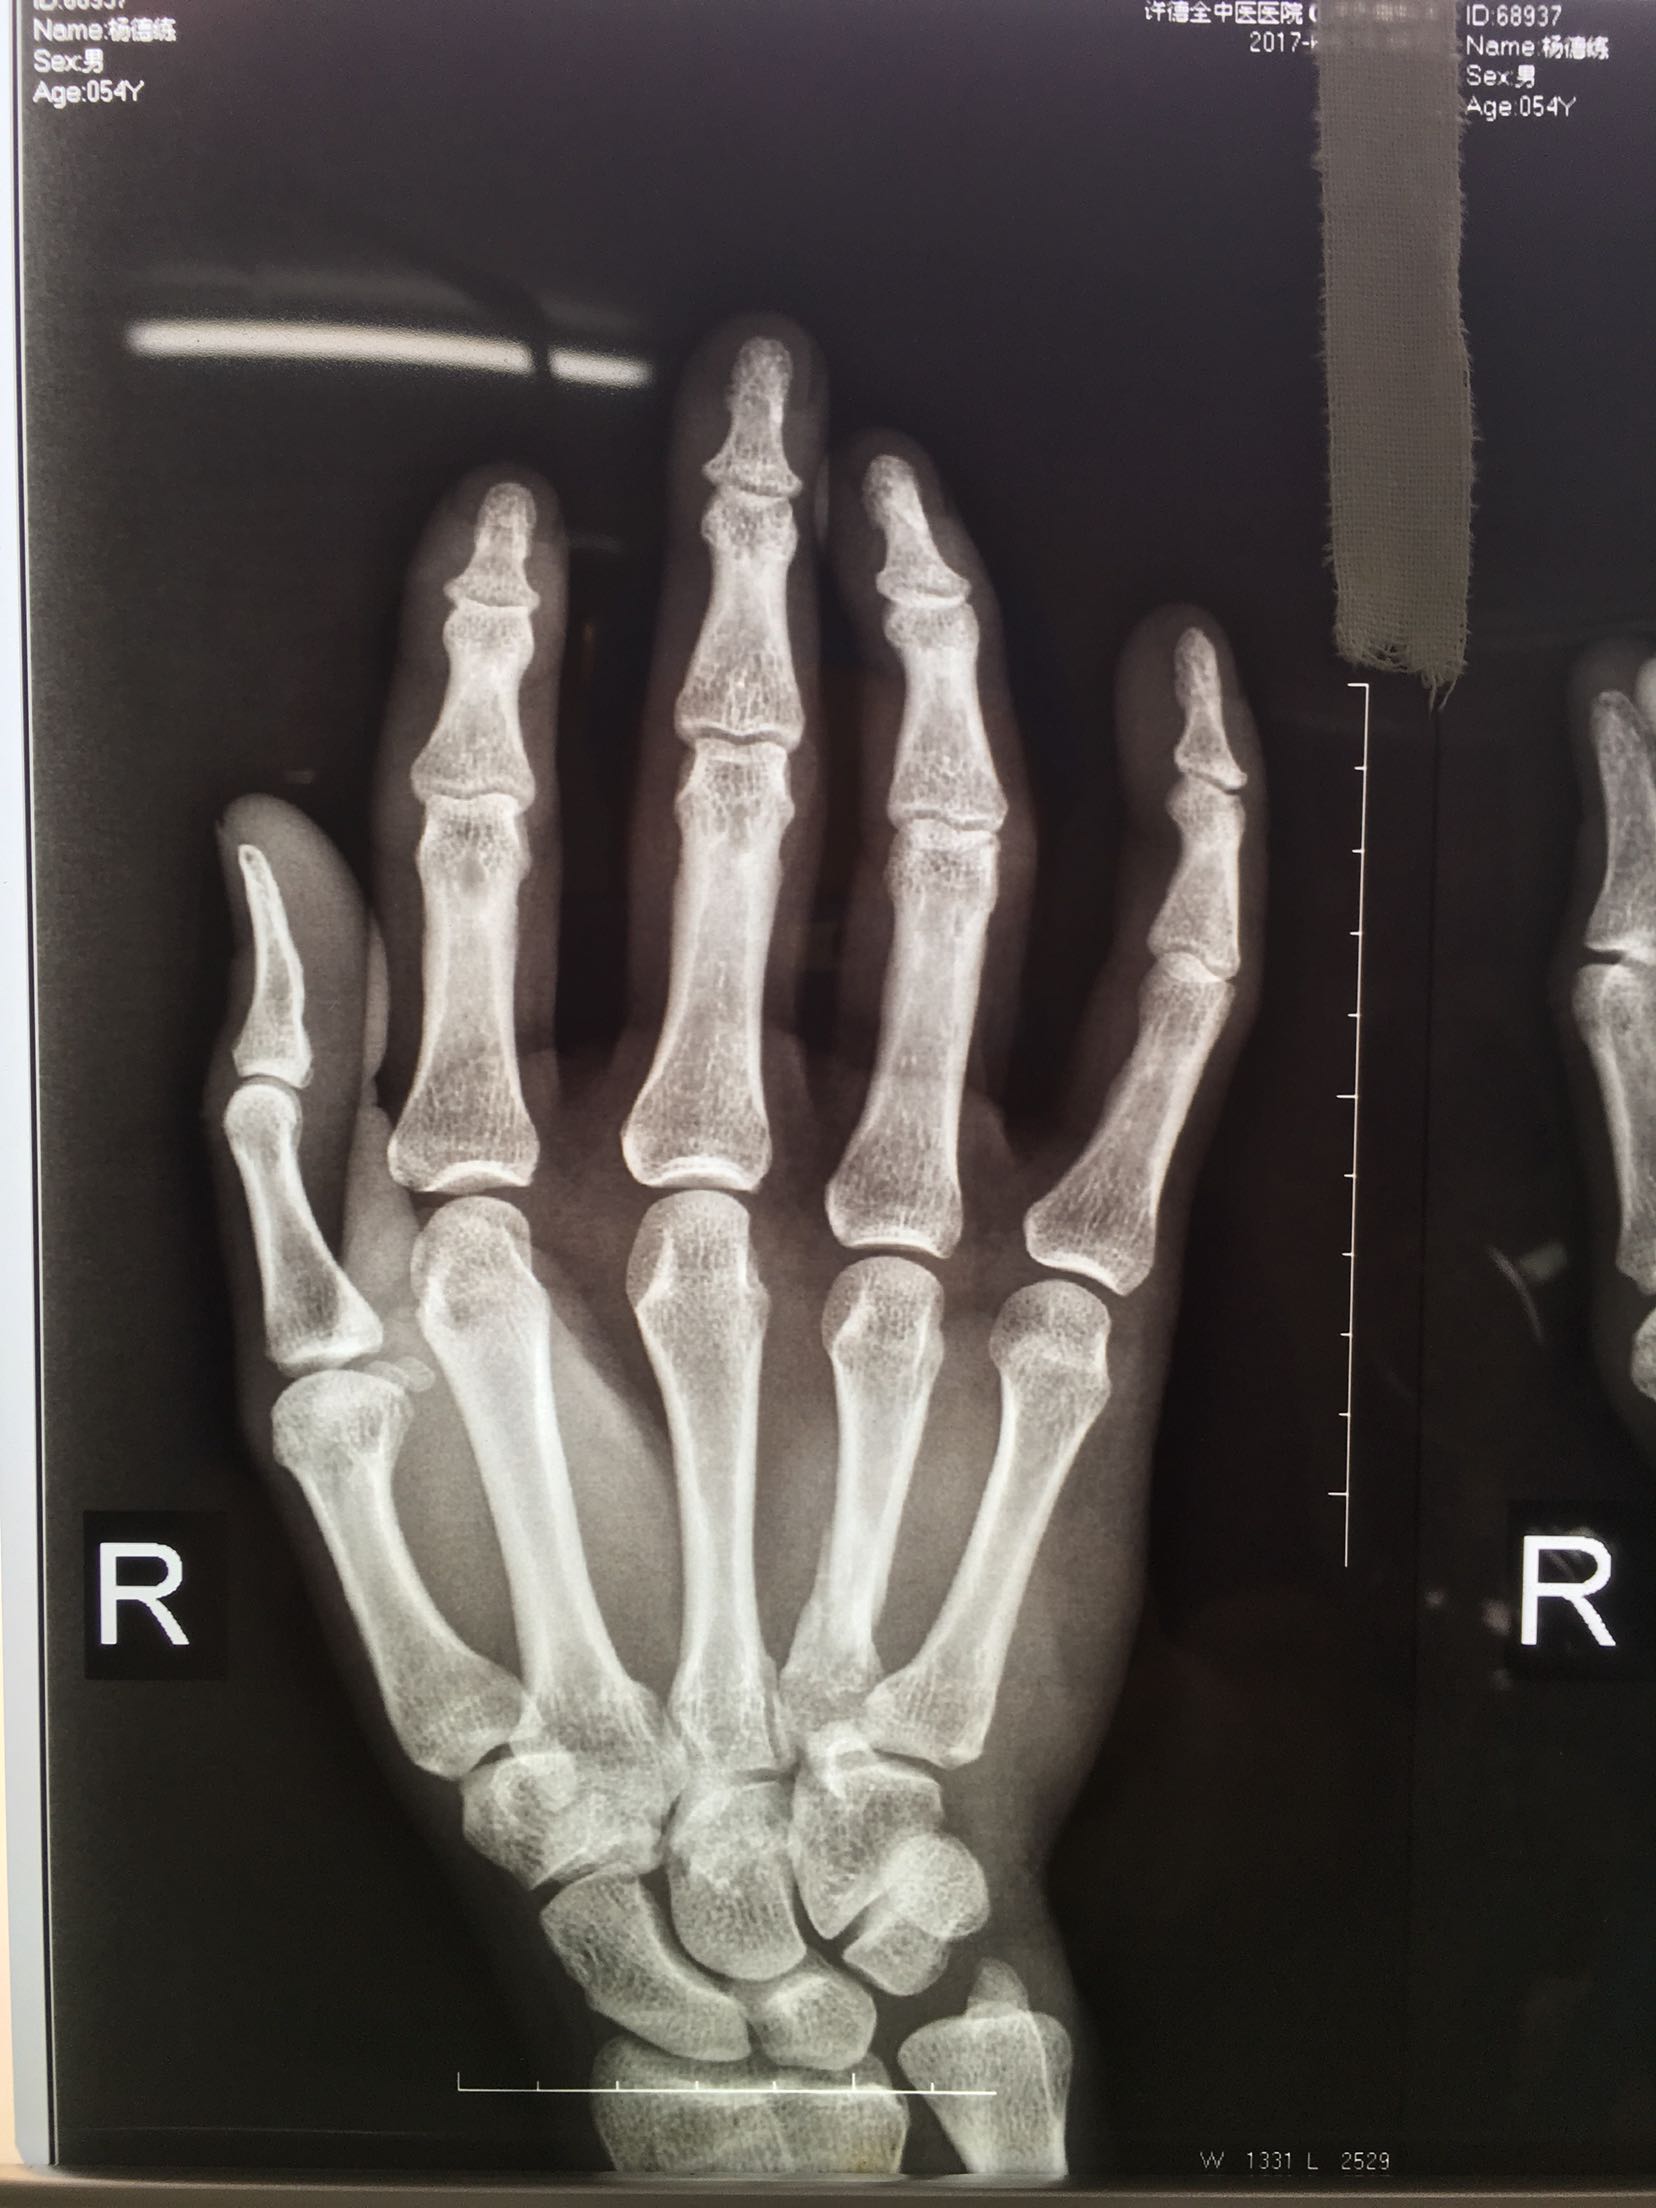

掌骨骨折微钢板固定

患者,男,52岁,摔伤后右手肿痛,活动受限4小时入院。

右手掌肿胀明显,皮色皮温正常,局部压痛,纵叩痛阳性,可及骨擦感,第四掌指关节活动受限,末梢血运感觉正常。

诊断 处理

完善检查,在臂丛麻醉下行切复内固定术,术后抗炎,消肿止痛处理。